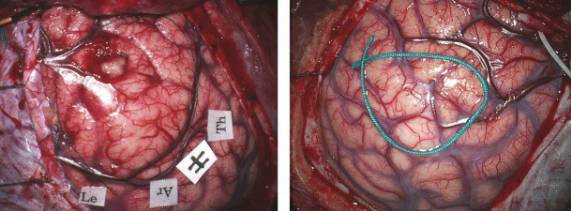

图5. 皮层低级别胶质瘤可导致其上覆盖皮质的形态学发生变化(左图)或无变化(右图)。左图显示右额叶运动前区皮层的扩大和矢状窦旁静脉向后移位。右图显示右额叶后部的肿瘤(绿色丝线标记边界)引起很小的皮层形态改变。